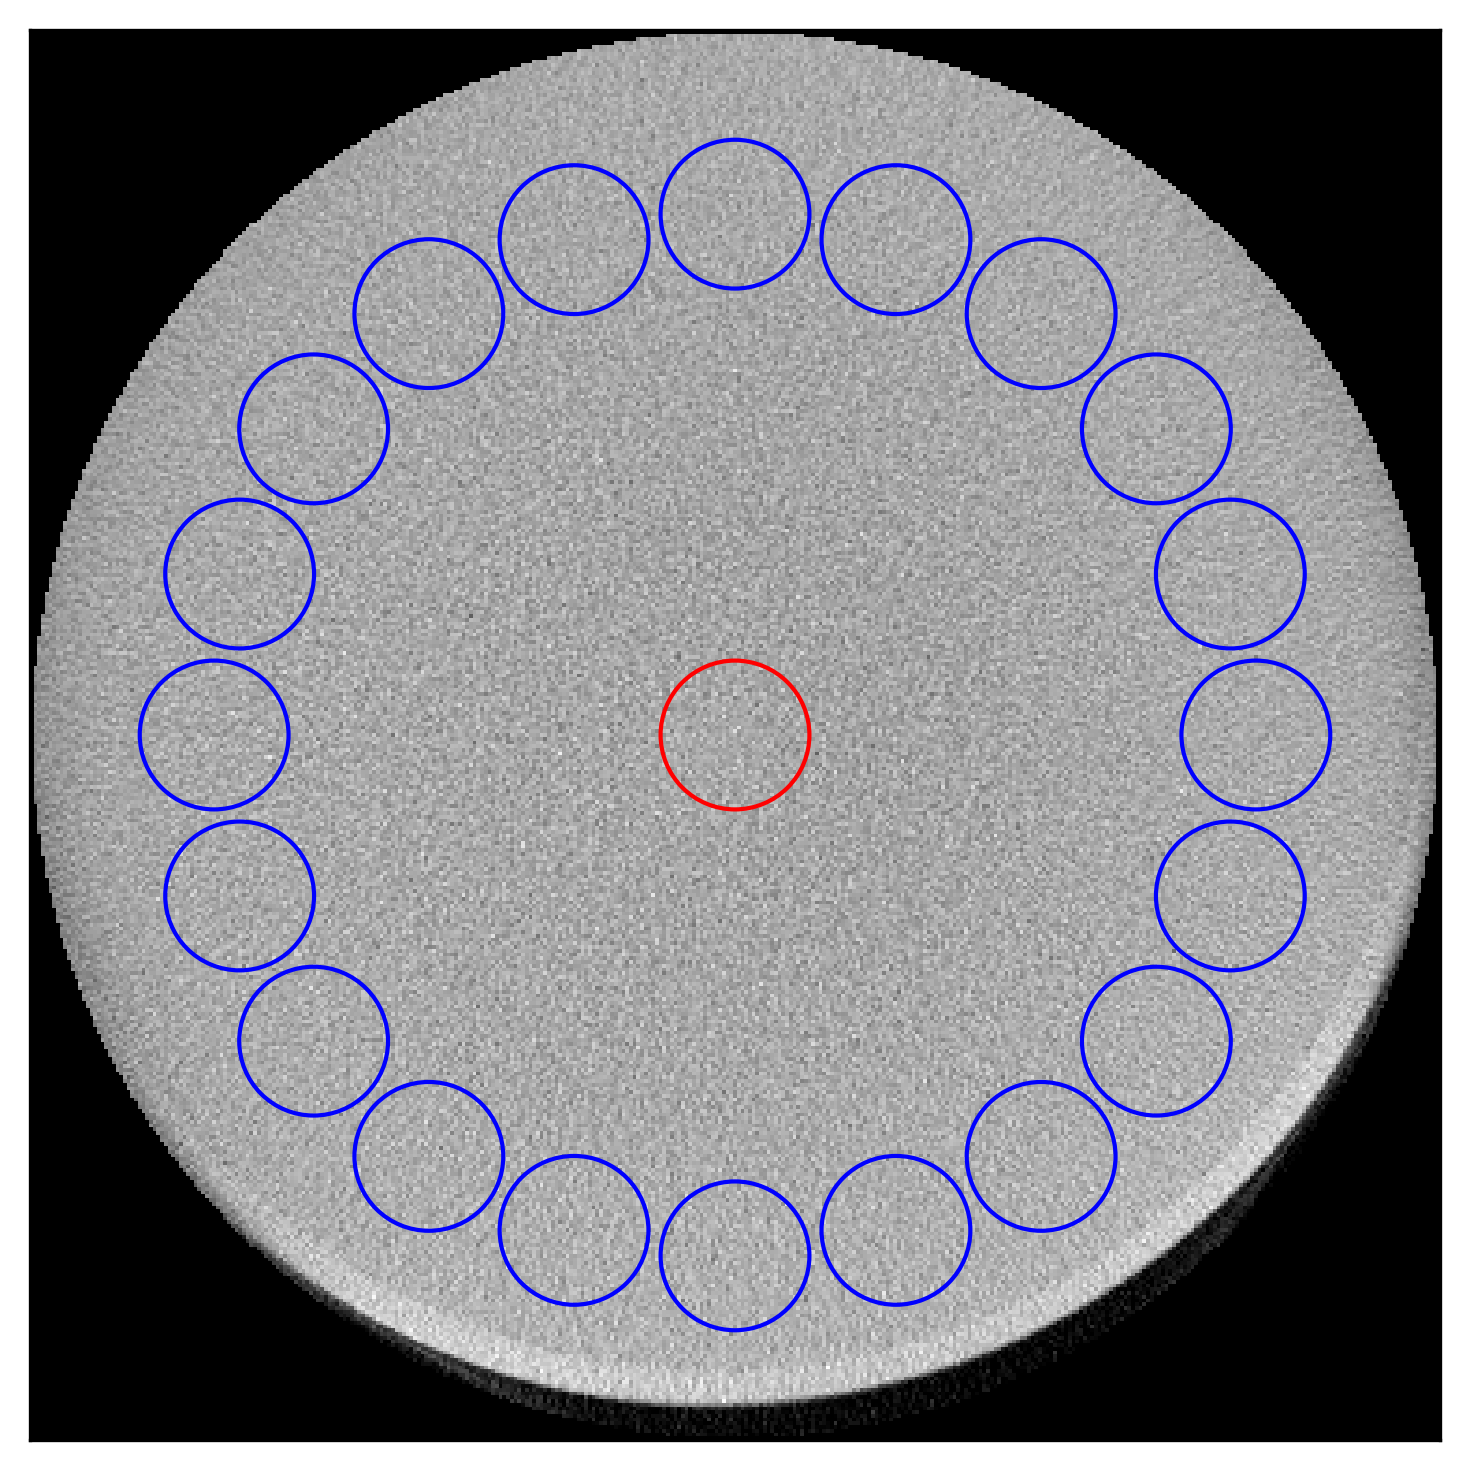

Refer to caption

(b) Middle axial slice from the water bottle scan showing the location of the central ROI (red) and 20 ROIs (blue) in the periphery, used to calculate image uniformity.

(b) Uniformity (HU) calculated for various methods for the selected ROIs from the water bottle scan.

method uniformity

uncorrected 8

net-320×256320\times 256 14

net-160×128160\times 128 17

net-80×6480\times 64 27

net-40×3240\times 32 16

net-20×1620\times 16 18

Figure 8: Image uniformity in the corrected images compared for the different methods.

Further, we compared the scatter estimation performance of five different networks, trained with five input sizes for the simulated projections. The net-40×3240\times 32 outperformed all the other networks showing least MSE (0.134±0.0090.134\pm 0.009) and comparable MAPE (3.85±0.103.85\pm 0.10) with only 310 MB of GPU memory, processing a batch size of 64 in just under 6 ms. In comparison, net-320×256320\times 256 took 90 ms with 3.9 GB GPU memory and had worse MAPE (4.42±0.184.42\pm 0.18 and MSE (0.20±0.0140.20\pm 0.014). Similar results were obtained for the simulated reconstructions after the scatter correction. Specifically, net-40×3240\times 32 had second lowest RMSE (8.96±2.908.96\pm 2.90), which was better than the RMSE (9.66±2.299.66\pm 2.29) of net-320×256320\times 256. However, net-160×128160\times 128 had slightly better RMSE of 8.85±2.928.85\pm 2.92. It is clear that the smaller input size significantly reduces the computational requirements while maintaining acceptable error rates. Which shows that the net-40×3240\times 32 configuration offers a good balance between performance and resource efficiency. Additionally, the uniformity is shown for the water jar and water bottle scans in Fig. 8. The difference between the uniformity values of the uncorrected images is significant, with the uniformity being 118 HU for the large water jar and 8 HU for the small water bottle. This discrepancy results from the large amount of scatter in the larger water jar compared to the smaller water bottle. An interesting observation is that while the neural network-based methods improved the uniformity in the water jar scan (18 HU), the uniformity worsened for the water bottle (16 HU). This can be attributed to the over-correction in the water bottle compared to the water jar since the training data did not include such small objects. Nonetheless, the net-40×3240\times 32 achieved comparable results to the other best performing networks for both scans.